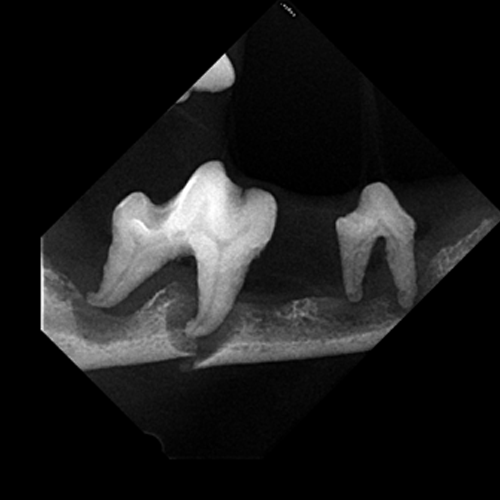

Lésions de résorption dentaire sur canine mandibulaire de chat